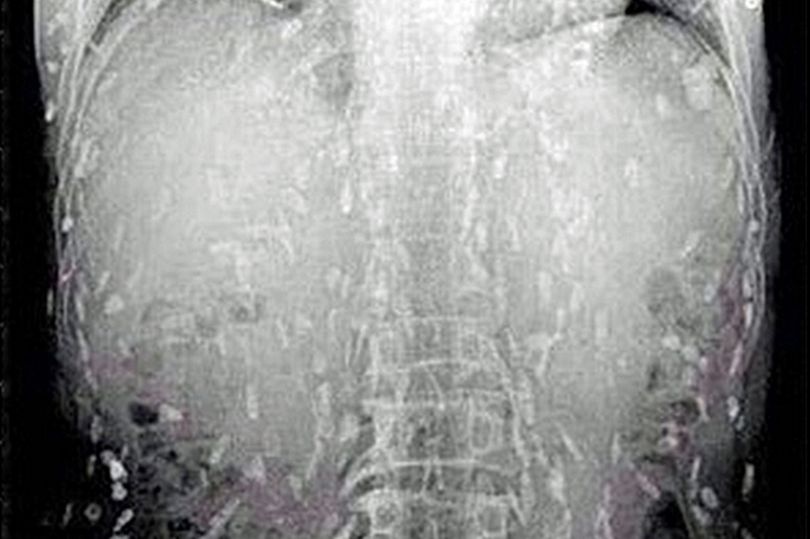

เว็บไซต์ข่าวมีร์เรอร์แชร์ภาพเอ็กซ์เรย์ชวนอึ้งของชายผู้รักการกินซูชิเป็นชีวิตจิตใจ ที่หารู้ไม่ว่าสิ่งที่ชื่นชอบกำลังทำให้ร่างกายของเขาถูกทำลาย หลังภาพเอ็กซ์เรย์ปรากฏว่าข้างในร่างกายเต็มไปด้วยพยาธิตัวตืด!

ชายชาวจีนผู้รักการกินซูชิรายหนึ่งมาพบแพทย์ หลังจากมีอาการปวดท้องและคันไปทั่วผิวหนัง และก็ต้องผงะ เมื่อภาพเอ็กซ์เรย์ที่ออกมาร่างกายของเขาเต็มไปด้วยพยาธิตัวตืด เป็นผลมาจากการกินซาซิมิมากเกินไป หลังจากเขาจับปลาในน้ำจืดมาแล่กินเองแบบดิบๆ

โดยแพทย์เชื่อว่าอาหารญี่ปุ่นประเภทเนื้อดิบและปลาดิบจะมีการปนเปื้อนสิ่งที่ไม่พึงประสงค์ที่ส่งผลให้มีการติดเชื้อปรสิตได้หลากหลายชนิด

พยาธิตัวตืด เกิดขึ้นจากการบริโภคเผลอไปบริโภคตัวอ่อนของพยาธิตัวตืดเข้าไป พบได้ในปลาที่อยู่ในแหล่งน้ำจืดเช่น แซลมอน (ซึ่งปกติเป็นปลาที่อยู่ในน้ำเค็มแต่จะมาวางไข่ในน้ำจืด) และมันสามารถอยู่รอดในร่างกายของมนุษย์ได้นานเป็นปี และวางไข่ทิ้งไว้ตามส่วนต่างๆของร่างกายและแพร่พันธุ์ได้อย่างรวดเร็ว

และอันตรายยิ่งเพิ่มขึ้นหากมันเคลื่อนตัวไปยังอวัยวะที่สำคัญจะดีกว่าถ้าเรากินอาหารที่ปรุงสุกแล้ว